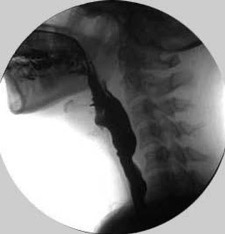

2. Modified Barium Swallow Study (Videofluoroscopy)

- The patient swallows food and liquids containing barium of different consistencies, and the process is recorded radiologically.

- The passage of food through the esophagus, pharynx, and larynx, as well as any pauses, obstructions, or aspiration risks, is observed in detail.

- This method is used to evaluate both the overall swallowing function and the structural condition of the esophagus.

- Radiation is used during the procedure, so time and dose are limited, but it provides very detailed anatomical and functional information.

- Videofluoroscopic swallowing assessment is performed in the radiology department under special radiation protection conditions.